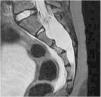

CSF hypotension arises in the context of a leak of CSF which causes negative intracranial pressure. Sacral fractures result from high-energy trauma which are frequently underdiagnosed. A ten-year-old boy presented with hip pain, after a fall. He mobilized both lower limbs, reported no leg pain, irradiation nor lack of sphincter control. The neurological examination was normal. When asked to stand, he began biparietal headache, nausea and vomiting, which improved laying down. CT scan showed an occult intrasacral meningocele; the MRI revealed collections of CSF along the spine, a S3 fracture with potential laceration of the meningocele and opening of a CSF fistula. Our diagnosis was the CSF hypotension, secondary to the fistula opening. The diagnosis was challenging. The child first presented with symptoms of CSF hypotension without evident cause. The discovery of the meningocele led us to hypothesize the opening of a fistula, a rare diagnosis, later confirmed by MRI.